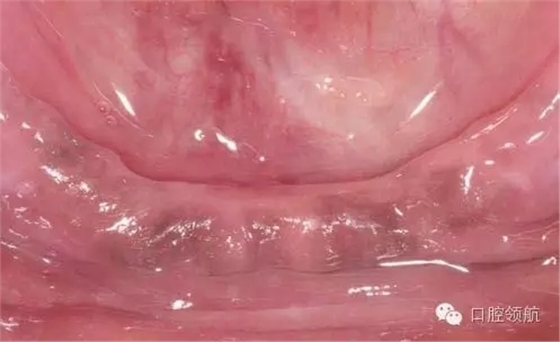

初診時(shí),口內(nèi)所見(jiàn)(圖1),曲面斷層片顯示(圖2),患者植入?yún)^(qū)骨量不足,前庭溝深度不足,附著齦的量不足。

圖1 初診時(shí)口內(nèi)所見(jiàn)。